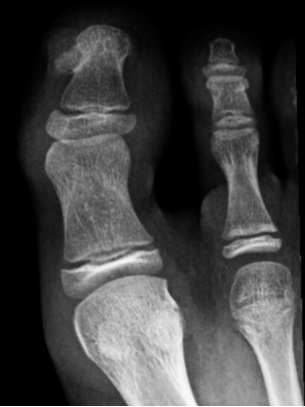

Niño de 11 años que fue valorado en la consulta de Pediatría por alteración de la uña del primer dedo del pie derecho sin traumatismo previo. Referían que había ido creciendo en los últimos seis meses y que le dolía al tocárselo o con el roce. En la exploración física se observó una tumoración subungueal hiperqueratósica con onicodistrofia, localizada en la zona dorsomedial del primer dedo del pie derecho (Fig. 1). Fue derivado a Dermatología para su valoración y con el juicio clínico de exostosis subungueal o fibroqueratoma digital/verruga vulgar se solicitó radiografía del dedo afecto (Fig. 2). En dicha prueba de imagen se confirmó la presencia de exostosis en la primera falange y se derivó a Traumatología para tratamiento quirúrgico.

El diagnóstico es fundamentalmente clínico y se confirma con la imagen radiológica, en la que se observaría una lesión exofítica de densidad ósea sin interrupción de la cortical, habitualmente localizada en el borde lateral interno de la falange distal3.